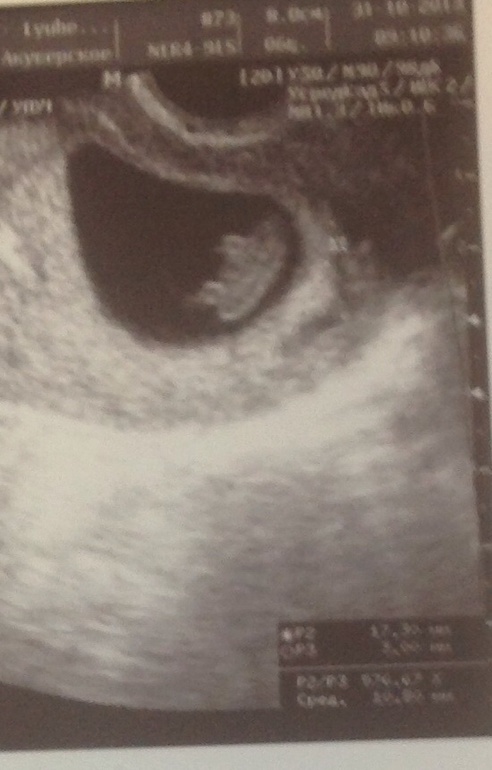

8 недель и 6 дней

Результаты: УЗИ, КТГ, доплера, скринингаВот результат нашего похода на узи!!!!! Мазни и выделений совсем нет!!! Отслойки нет !!! Наблюдается положительная динамика!!!! Малыш уже 1,98см!!!! Врач сказала что у нас все хорошо!!!! Уже у нас видны ручки и ножки!!!!! И пуповина формируется !!!!! Вышла с узи с огромным чувством радости и счастья!!!! Аааа... Совсем забыла!!! 19 ноября на 1 скрининг!!!!!